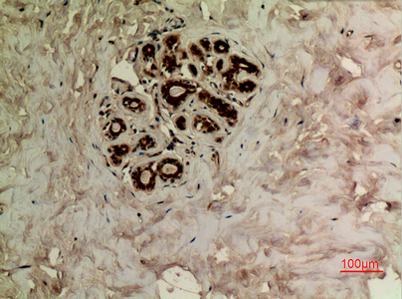

Tubulin α (Acetyl Lys40) rabbit pAb

Product name: Tubulin α (Acetyl Lys40) rabbit pAb

Dilutions: Western Blot: 1/500 - 1/2000. IHC-p: 1:100-300 ELISA: 1/20000. Not yet tested in other applications.

Immunogen: The antiserum was produced against synthesized Acetyl-peptide derived from human TUBA1A around the Acetylation site of Lys40. AA range:1-50

Cellular localization: Cytoplasm, cytoskeleton.